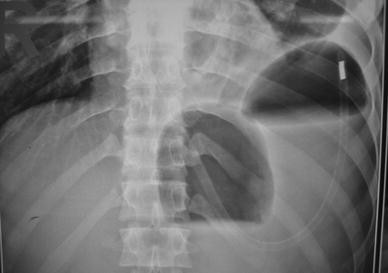

Medical News Radiology Mcqs For Usmle Aipgee And Plab Double Bubble Sign Causes Include A Congenital Obstruction Duodenal Web Duodenal Atresia Duodenal Stenosis Annular Pancreas B

シングルバブル、ダブルバブル、トリプルバブルサインの違い なになにバブルサインとは、消化管が閉鎖される疾患のレントゲン所見のこと。 シングルバブルサイン ダブルバブルサイン トリプルバブルサイン 画像 出典 出典:105D41 出典スクリーン ダブルバブル クリア honda vtr1000f '97 〜 '05 カラー:クリア タイプ:ダブルバブル ご注意 写真は実際の製品と異なる場合がございます。 16年3月22日からの新価格です。Double(ダブル)は、日本の女性 歌手、ソングライター、takakoによるソロ・プロジェクト。 姉妹デュオとして1998年にデビューしたが、1999年に姉のsachikoが急逝したため、以降は現在の形態となった。 06年からはdj lilly aka double(ディージェイ・リリー・エーケーエー・ダブル)名義